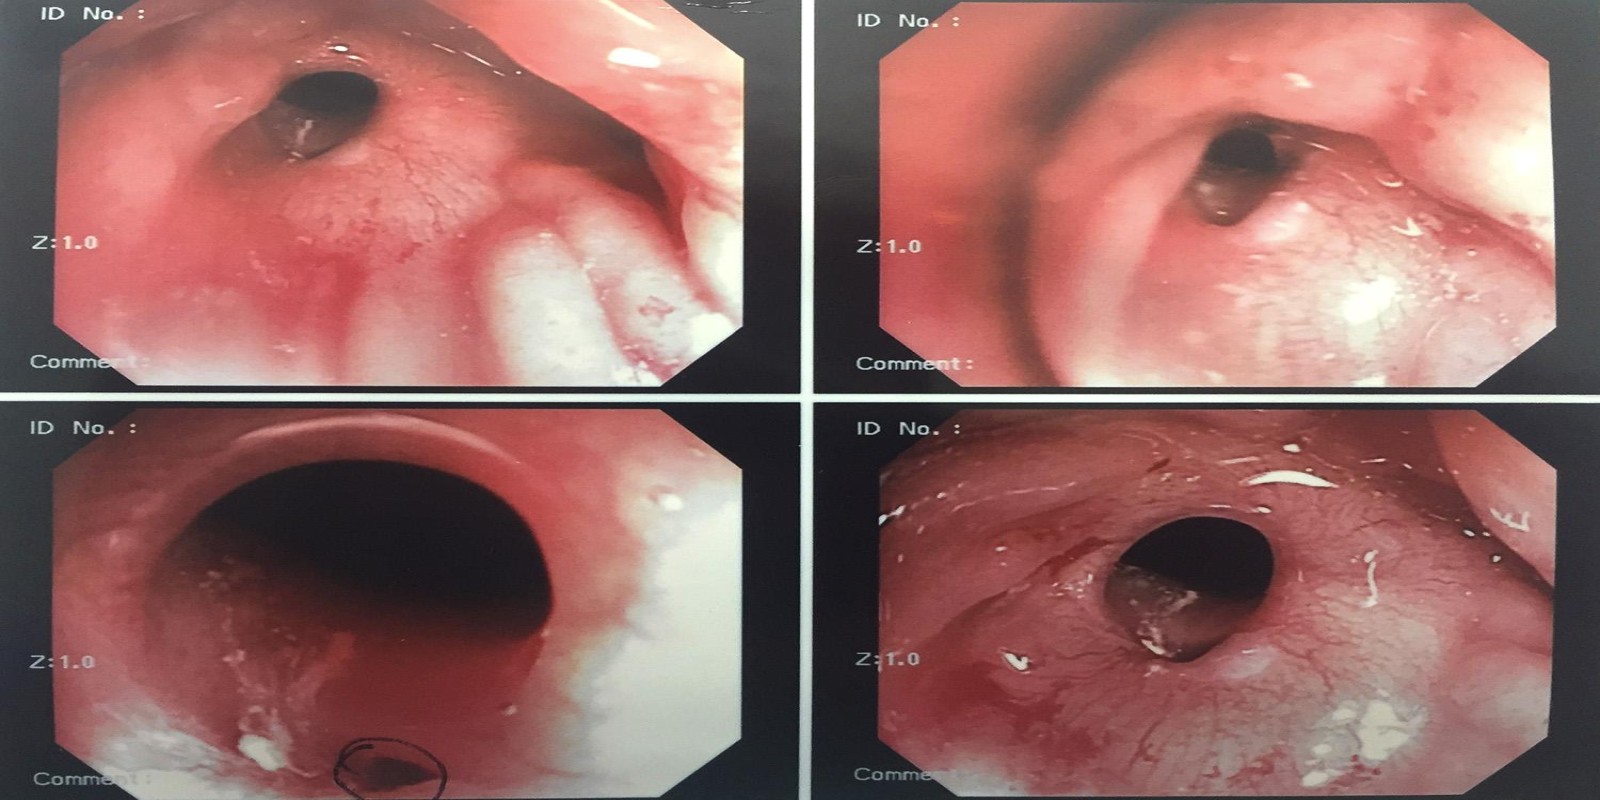

Caso Código 238B de Fístula reto-vaginal

Cod.: 238B

Caso Código 238C de Fístula reto-vaginal

Cod.: 238C

Caso Código 238D de Fístula reto-vaginal

Cod.: 238D